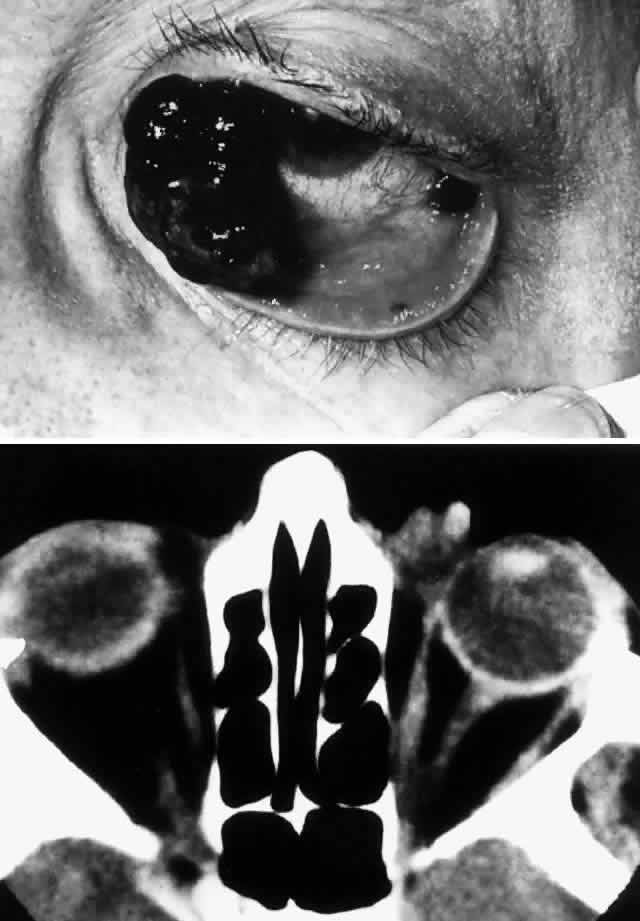

Sebaceous carcinoma has achieved a notorious reputation because it can be difficult to diagnose correctly in the early stages. Clinically, the tumor may masquerade as a chronic chalazion, blepharoconjunctivitis, basal cell carcinoma, keratoconjunctivitis, or very rarely as a primary orbital tumor. Another cause for confusion has been pathologic misdiagnosis of sebaceous carcinoma, most commonly being mistaken for basal cell carcinoma or squamous cell carcinoma. Increasing awareness of the characteristic presentation, along with earlier and more accurate clinical and pathologic diagnosis, has decreased the mortality associated with this tumor. The blepharoconjunctivitis associated with this lesion is the result of intraepithelial (pagetoid) spread of sebaceous carcinoma. The usual clinical appearance is a thickening of the conjunctiva associated with frank injection in areas of invasion (Fig. 9). A careful biomicroscopic examination reveals yellowish, plaque-like foci within the affected epithelium.

Fig. 9. A 79-year-old man had been treated for several years for chronic blepharoconjunctivitis. On examination, he had thickening of upper and lower lid margins, diffuse symblepharon, conjunctival thickening, injection, and yellowish plaque-like foci (A). Conjunctival biopsy confirmed invasive sebaceous cell carcinoma, and subtotal exenteration was performed. Tumor invasion along the globe (B) (H & E, × 32) and into muscle (C) (H & E, × 80) was noted.